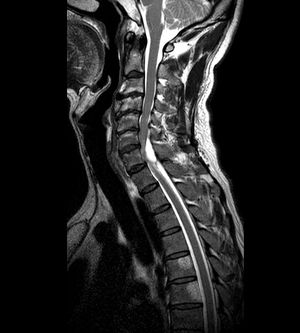

A 49-year-old male suffered from mild right hand numbness for several months. The cervical MRI showed one well-defined lesion lobular lesion in right side posterior epidural space of C5-6.